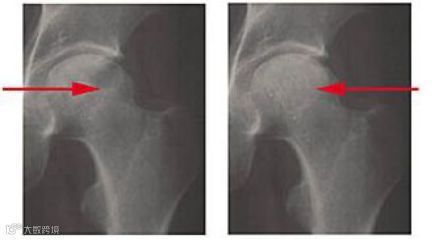

3.髓芯减压植骨术联合脐带间充质干细胞移植治疗股骨头坏死

沈阳医学院附属中心医院骨外四科选择2010年5月至2013年5月住院的股骨头坏死病例27例患者,进行髓芯减压植骨术联合脐带MSCs移植治疗。27例患者术后12~20个月 (平均18个月) 随访, 按Harris髋关节功能评分, 疼痛消失, 能从事各种劳动, X线片或MRI显示股骨头基本正常23髋 (76.7%) ;疼痛明显减轻, 行走基本正常或者轻微跛行7髋 (23.3%) ;行走间距延长28髋 (93.3%) , 髋关节功能障碍明显好转18髋 (60%) 。

髓蕊减压术加脐带间充质干细胞移植治疗股骨头坏死,有效再造坏死区骨质。